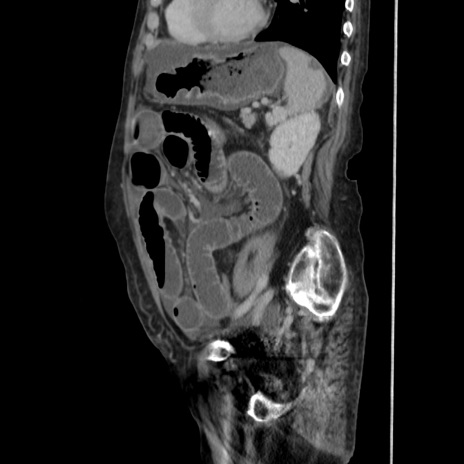

症例31(矢状断像)

【症例】80歳代 女性

【主訴】腹部膨満感

【現病歴】他院にて肝硬変にてフォロー中。1週間前から便秘、腹部膨満感、臍部腫瘤あり受診となる。

【既往歴】肝硬変

【身体所見】腹部膨隆あり、皮膚変化なし、疼痛なし。

【データ】WBC 4600、CRP 0.25